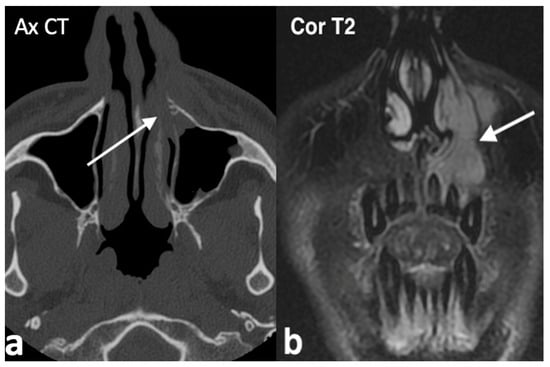

3.1.2. Rinolith